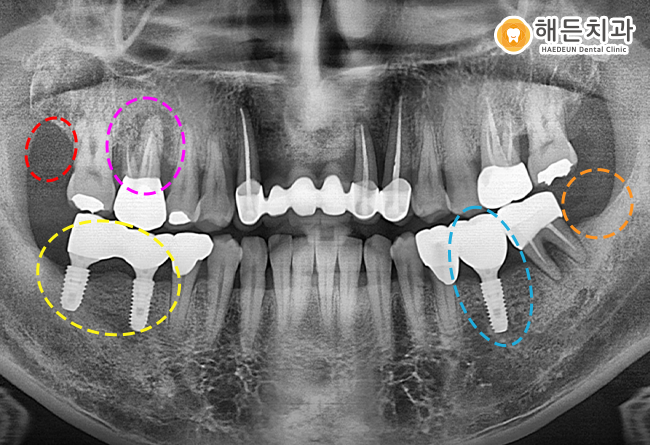

정밀검진을 위해 파노라마 사진을 촬영하여 확인해보니,

환자분이 불편감을 느끼는 부위는 상태가 너무 좋지 않았습니다.

오른쪽 위의 맨 후방에 위치하고 있는 사랑니는 충치 진행이 너무 심하여 발치가 필요한 상태였습니다.

그리고 오른쪽 아래 큰 어금니는 과거에 신경치료를 받아 덮어 씌운 치아인데,

뿌리 끝 염증이 심해 더 이상 살리기 어려워 해당 치아 또한 발치가 필요한 경우였습니다.

원래 건강한 뼈는 하얗게 차있어야 하는데,

노란색 동그라미 표시를 보시면 뿌리 끝이 까맣게 보이는 것을 확인하실 수 있습니다.

빨간색 동그라미 표시의 사랑니는 발치를 진행하기로 하였고,

노란색 동그라미 표시의 치아는 발치를 진행하고, 앞의 상실된 부위와 함께 임플란트 치료를 진행하기로 했습니다.

그리고 왼쪽 아래 어금니의 가장 후방에 있는 주황색 동그라미 표시의 사랑니는 발치하고,

왼쪽 아래 상실된 부위에 임플란트 식립을 함께 진행하기로 했습니다.